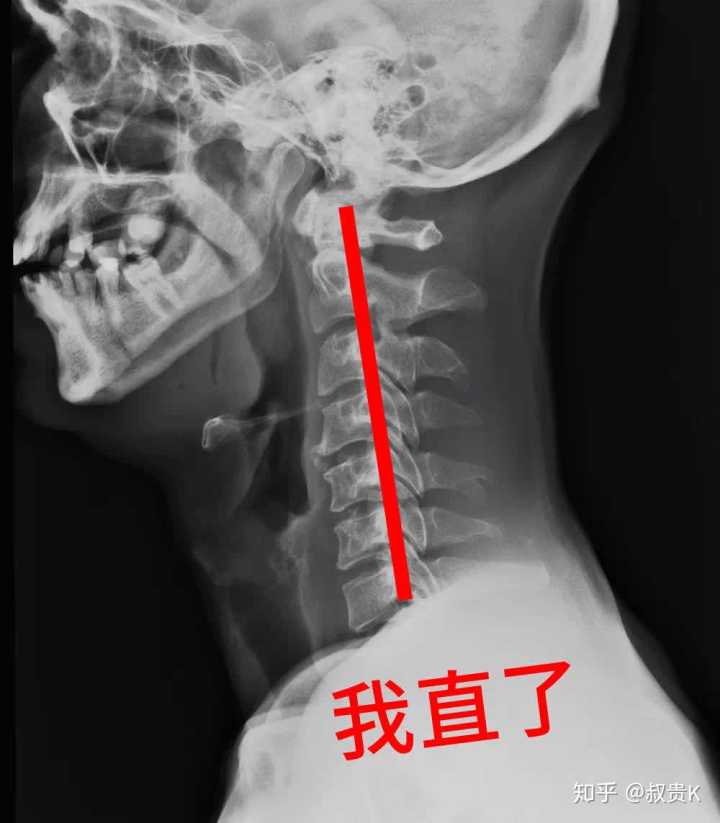

x光正位样片(2)侧位曲度的改变颈椎发直,生理前突消失或反弯曲.

我们先来看一张正常颈椎曲度的x光片.